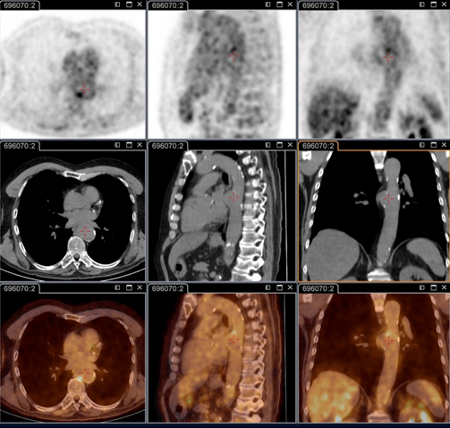

tomografia por emissão de pósitrons (PET)/tomografia computadorizada (TC) com 18-fluordesoxiglucose (FDG)

Exame

Essencial para identificar infecções focalizadas persistentes.[80]

É capaz de decifrar endocardite, infecção vascular, linfadenite e infecção osteoarticular; essas doenças não podem ser identificadas sem essa técnica.

Agora faz parte do check-up anatômico padrão em pacientes com sintomas persistentes e/ou sorologia elevada persistente e/ou reação em cadeia da polimerase positiva no sangue/soro, ou qualquer amostra com quadro clínico não consistente com infecção primária.[3]

É especificamente recomendada em pacientes: com febre Q aguda com IgG de fase 1 ≥1:800 persistente e/ou sinal de evolução desfavorável; com febre Q aguda e história de enxerto vascular ou aneurisma vascular; ou com sorologia inexplicada (IgG na fase 1 ≥1:800) ou suspeita clínica de infecção persistente.

Isso também é útil para identificar infecção em pacientes com prótese vascular e/ou aneurisma, e para identificar candidatos a cirurgia de ressecção dos tecidos vasculares infectados.[Figure caption and citation for the preceding image starts]: Endocardite por febre Q diagnosticada na PET: PET/TC com 18-fluordesoxiglucose. Neste paciente assintomático com história de valva cardíaca e sorologia elevada, a PET permitiu diagnosticar endocardite aórtica na valva nativa com aneurismas micóticos da aorta torácica e lombarInstitut Hospitalo-Universitaire Méditerranée Infection (obtido consentimento do paciente) [Citation ends].

[Figure caption and citation for the preceding image starts]: Aneurisma micótico na aorta torácica da febre Q diagnosticado na PET: PET/TC com 18-fluordesoxiglucose. Neste paciente assintomático com história de valva cardíaca e sorologia elevada, a PET permitiu diagnosticar endocardite aórtica na valva nativa com aneurismas micóticos da aorta torácica e lombarInstitut Hospitalo-Universitaire Méditerranée Infection (obtido consentimento do paciente) [Citation ends].

[Figure caption and citation for the preceding image starts]: Aneurisma micótico na aorta lombar da febre Q diagnosticado na PET: PET/TC com 18-fluordesoxiglucose. Neste paciente assintomático com história de valva cardíaca e sorologia elevada, a PET permitiu diagnosticar endocardite aórtica na valva nativa com aneurismas micóticos da aorta torácica e lombarInstitut Hospitalo-Universitaire Méditerranée Infection (obtido consentimento do paciente) [Citation ends].

Resultado

positivo na infecção focalizada persistente (por exemplo, valva cardíaca, foco vascular da linfadenite, linfonodos, foco osteoarticular)